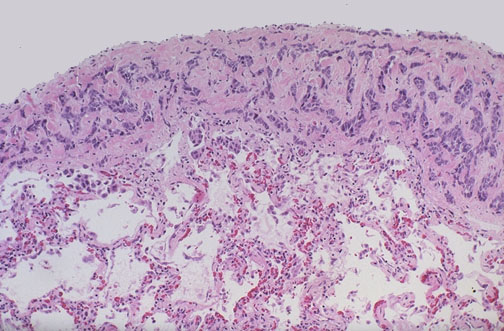

A focus of metastatic carcinoma from breast is seen on the pleural surface of the lung. Such pleural metastases may lead to pleural effusions, including hemorrhagic effusions, and pleural fluid cytology can often reveal the malignant cells.